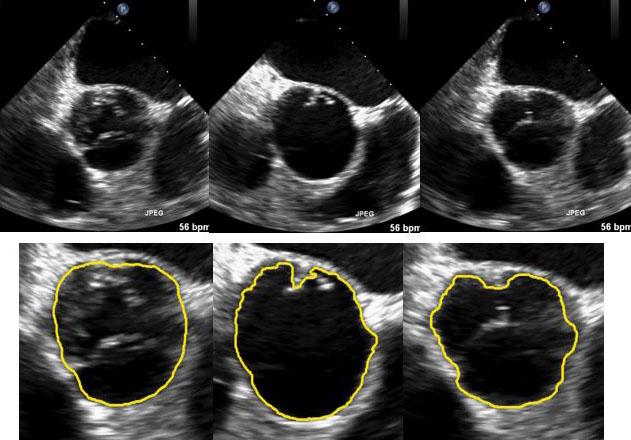

Image segmentation, the process of separating a digital image into multiple sections for individual examination, is frequently used in medical image analysis. For example, segmentation in ultrasound footage helps identify boundaries and regions of interest (ROI) that facilitate image interpretation. Efficient segmentation of ultrasound videos, however, is often complicated by low contrast, shadow effects, and complex "noise" statistics (unexplained variations). In addition, real-time applications such as navigation during operational surgery require efficient algorithms.

In an article published this month in the SIAM Journal on Imaging Sciences , authors Jiulong Liu, Xiaoqun Zhang, Bin Dong, Zuowei Shen, and Lixu Gu propose a video segmentation model to recognize ROI in ultrasounds. "The proposed model aims to track a moving boundary in ultrasound video efficiently and robustly, with a mathematically-sound framework," says Zhang. "Specifically, we tackle the problem by using wavelet frames and incorporating the noise statistics under a variational framework. The continuity and regularity of the moving boundary is effectively incorporated via weighted regularization, without introducing a heavy computational burden. The overall method can be efficiently solved with a recently-developed fast algorithm, making it useful in real-time clinical applications."

Liu et al. also chose to incorporate wavelet frames, which collect more detail than other variational methods and efficiently segment low-quality footage, such as ultrasound video. This is especially true when the image includes features at various scales. "Wavelet frame regularization is used because the geometric structures and singularities in different scales can be identified and extracted efficiently from complex noise environments in the wavelet domain," says Shen. "It allows us to track and sharpen geometric shapes when they are segmented automatically through sequential images in the video."

Liu et al. apply their model to two ultrasound video data sets and obtain numerical results, which confirm the model's ability to efficiently track ROI. "Ultrasound imaging is an important modality in clinical application due to its low cost and portability," says Liu. "However, its related analysis for accurate diagnosis and monitoring is still challenging due to low image quality, artifacts, and noise. The numerical results on real ultrasound data sets demonstrate that the proposed wavelet frame model with distance prior can track the regions of interest effectively, in terms of both segmentation quality and computational time." The results compare favorably with other approaches.